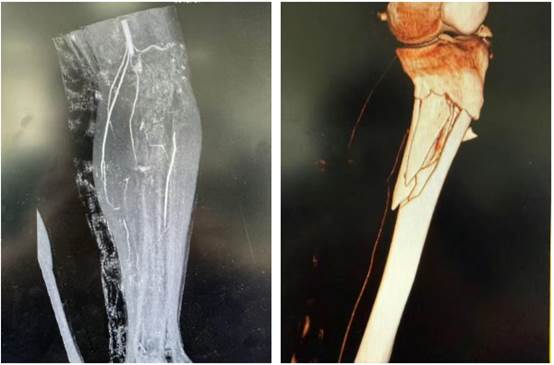

患者到院后,创伤外科值班医生王园迅速接诊,检查发现患者左下肢严重畸形、骨折断端外露,足背动脉搏动消失、皮肤苍白冰冷——提示下肢大血管损伤、肢体濒临坏死!时间就是生命!影像中心同步启动紧急检查绿色通道,CTA(CT 血管成像)结果迅速明确:腘动脉下段、左胫前动脉、胫后动脉及腓动脉上段未显影,确诊为「左胫腓骨开放性粉碎性骨折合并下肢主要血管断裂」。

在显微镜下,手术团队展开了高难度精细操作,实施「骨折外固定支架固定 + 胫前动脉吻合术 + 胫后动脉血栓取出及吻合术」。历经 5 小时鏖战,成功修复断裂的胫前动脉,清除胫后动脉血栓并精准吻合,终于成功重建下肢生命通道!目前患者生命体征平稳,受损肢体血运恢复良好。